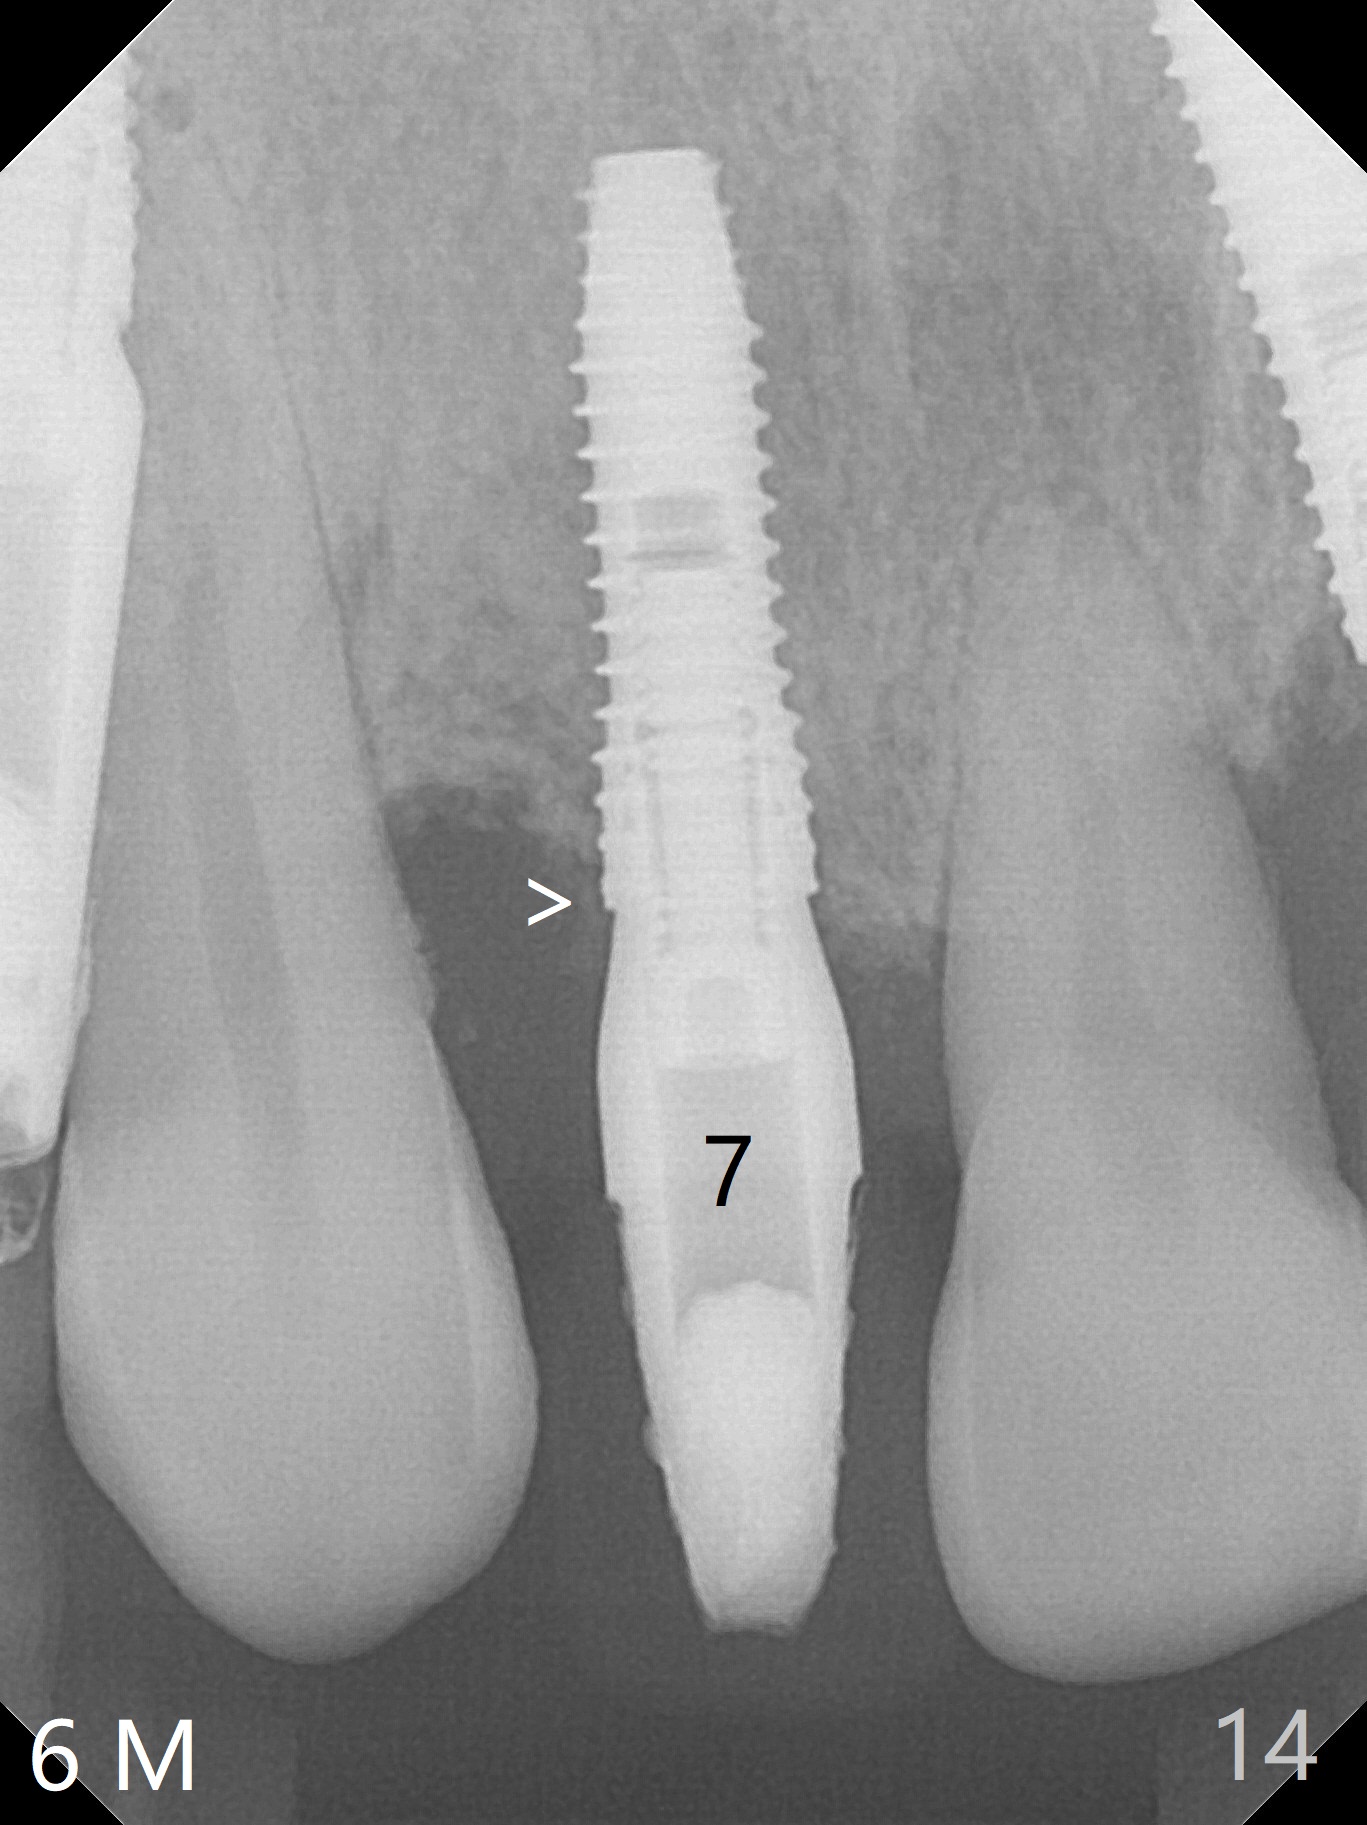

The patient returns 8 days postop, uncomfortable with overhang in the provisional (Fig.10 *). The sockets appear to be healing with loose bone graft (Fig.11) when the provisional is removed for trimming (Fig.12). Six (for #7,13) and seven (#9-11,15) months postop, the soft (Fig.13,17) and hard (Fig.14-16,18) tissues heal. It appears that the trajectory at #9,11 and 13 should be changed by using angled abutments (Fig.18,19 (panoramic X-ray taken 2 months earlier)) before provisional and final restoration.

There is 1-2 thread exposure mesial and distal at #10 two years postop (Fig.20'), which may be related to the small fistula labially (Fig.20 >). It appears that the implant at #10 was placed too high (Fig.21) and labially (Fig.22). In fact the bridge fractures between #12 and 13 during pandemic.